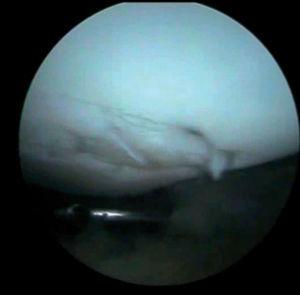

Figura 6 Artroscopia. Cuerpos libres alrededor de los ligamentos cruzados y en otras localizaciones intraarticulares.

Se practica artroscopia, en la que se observan (figs. 2, 4, 6-8):

• Múltiples fragmentos condrales libres de bordes agudos, que se identifican como recientes y de bordes redondeados que se catalogan como antiguos.

• Lesión condral anfractuosa extensa, con fragmentos inestables en cresta de la rótula y en faceta externa, de grado III.

• Resto de estructuras intraarticulares íntegras.